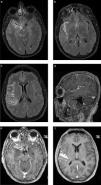

El patrón ordenado o en “doble anillo” de los productos de fagocitosis que determinan la presencia de este artificio es muy útil en el diagnóstico diferencial de las lesiones con patrón de realce anular, sobre todo con lesiones tumorales de alto grado con necrosis, como el glioblastoma multiforme14 (fig. 2).

Absceso cerebral bacteriano inespecífico, confirmado luego del drenaje quirúrgico. Los cortes seleccionados de la RM en el plano axial demuestran la utilidad de (a) la secuencia de susceptibilidad magnética, (b) la SE ponderada en T1 con contraste, (c) la difusión y (d) el mapa de ADC. En la susceptibilidad magnética se identifica el aspecto típico de la cápsula bacteriana con un patrón en diana o de doble pared, debido al depósito ordenado de productos de degradación de la hemoglobina. La lesión presenta el típico realce en anillo fino, regular, completo y sin nódulos, con un centro necrótico con un intenso fenómeno de restricción en la difusión.

Se ha establecido la presencia de un intenso fenómeno de restricción en el centro de los AC bacterianos inespecíficos, que ha sido relacionada con la viscosidad del pus y su escasa celularidad18,19(fig. 2).

La presencia de restricción en una lesión con realce en anillo permite establecer el diagnóstico de AC bacteriano (con niveles de especificidad cercanos al 100%) y lo diferencia, sobre todo, de lesiones tumorales con necrosis o contenido quístico18,20,21 (fig. 4). Incluso, este hallazgo se ha señalado como patognomónico del AC, a pesar de que puede encontrarse en otro tipo de lesiones, como algunas metástasis con contenido de alta viscosidad o glioblastomas con hemorragia22.